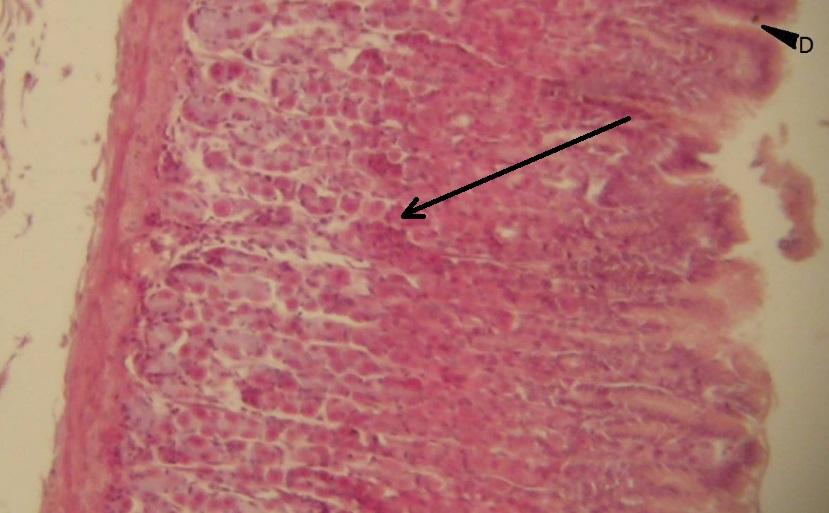

Pytanie 393

komórka okładzinowa - okrągła, intensywnie różowa (dno i trzon żołądka)

Pytanie 394

komórka główna - znajdująca się w dnie i szyjce gruczołów cewkowych (dno i trzon żołądka)